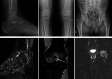

Complex regional pain syndrome (CRPS) and bone marrow edema syndrome (BMES) are two rare conditions that are still being discussed. They are generally considered as two distinct entities, yet they share similarities such as a homogeneous bone marrow edema is also often found in the early phase of CRPS. We present the case of a 41-year-old man with CRPS after a foot fracture followed by the development of painful BMES of the ipsilateral knee and hip a few weeks later. The search for another pathology was negative. After pamidronate infusions, the evolution was spectacular: the disappearance of hip pain at 1 month and more than 50% reduction in knee and foot pain at 2 months. At final follow-up (1 year), the patient was asymptomatic. This case reinforces the idea of a possible link between CRPS and BMES probably through similar trabecular bone involvement. Imaging remains useful in diagnosis of CRPS.